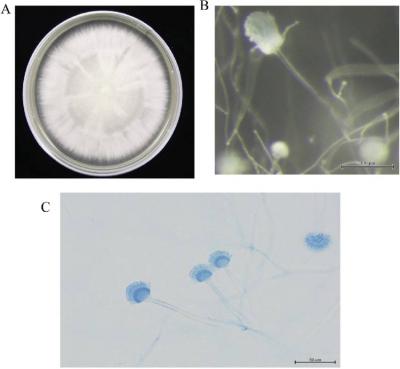

दिल्लीत नव्या फंगसमुळे होणाऱ्या मृत्यूंमुळे चिंतेत भर पडली आहे. एम्समध्ये दोन रुग्णांना एस्परजिलियस लेंटुलस नावाच्या फंगसची लागण झाली. या प्रकारच्या फंगसवर कोणत्याही औषधाचा परिणाम होत नाही.

क्रॉनिक ऑब्स्ट्रक्टिव पल्मोनरी डिजीजचा सामना करत असलेल्या दोन्ही रुग्णांचा उपचारादरम्यान मृत्यू झाला. एस्परजिलियस लेंटुलस फुफ्फुसावर परिणाम करतं. २००५ मध्ये वैद्यकीय जगताला या फंगसची औषध पटली. तेव्हापासून आतापर्यंत अनेक देशांमध्ये एस्परजिलियस लेंटुलसचे रुग्ण आढळून आले आहेत.

भारतात पहिल्यांदाच एस्परजिलियस लेंटुलसचे रुग्ण आढळून आले आहेत. इंडियन जर्नल ऑफ मेडिकल मायक्रोबायोलॉजीमध्ये (IJMM)प्रकाशित झालेल्या अहवालानुसार एस्परजिलियस लेंटुलसमुळे मृत्यूमुखी पडलेल्या एका रुग्णाचं वय ५० ते ६० वर्षांदरम्यान, तर दुसऱ्या रुग्णाचं वय ४५ वर्षांपेक्षा कमी होतं.